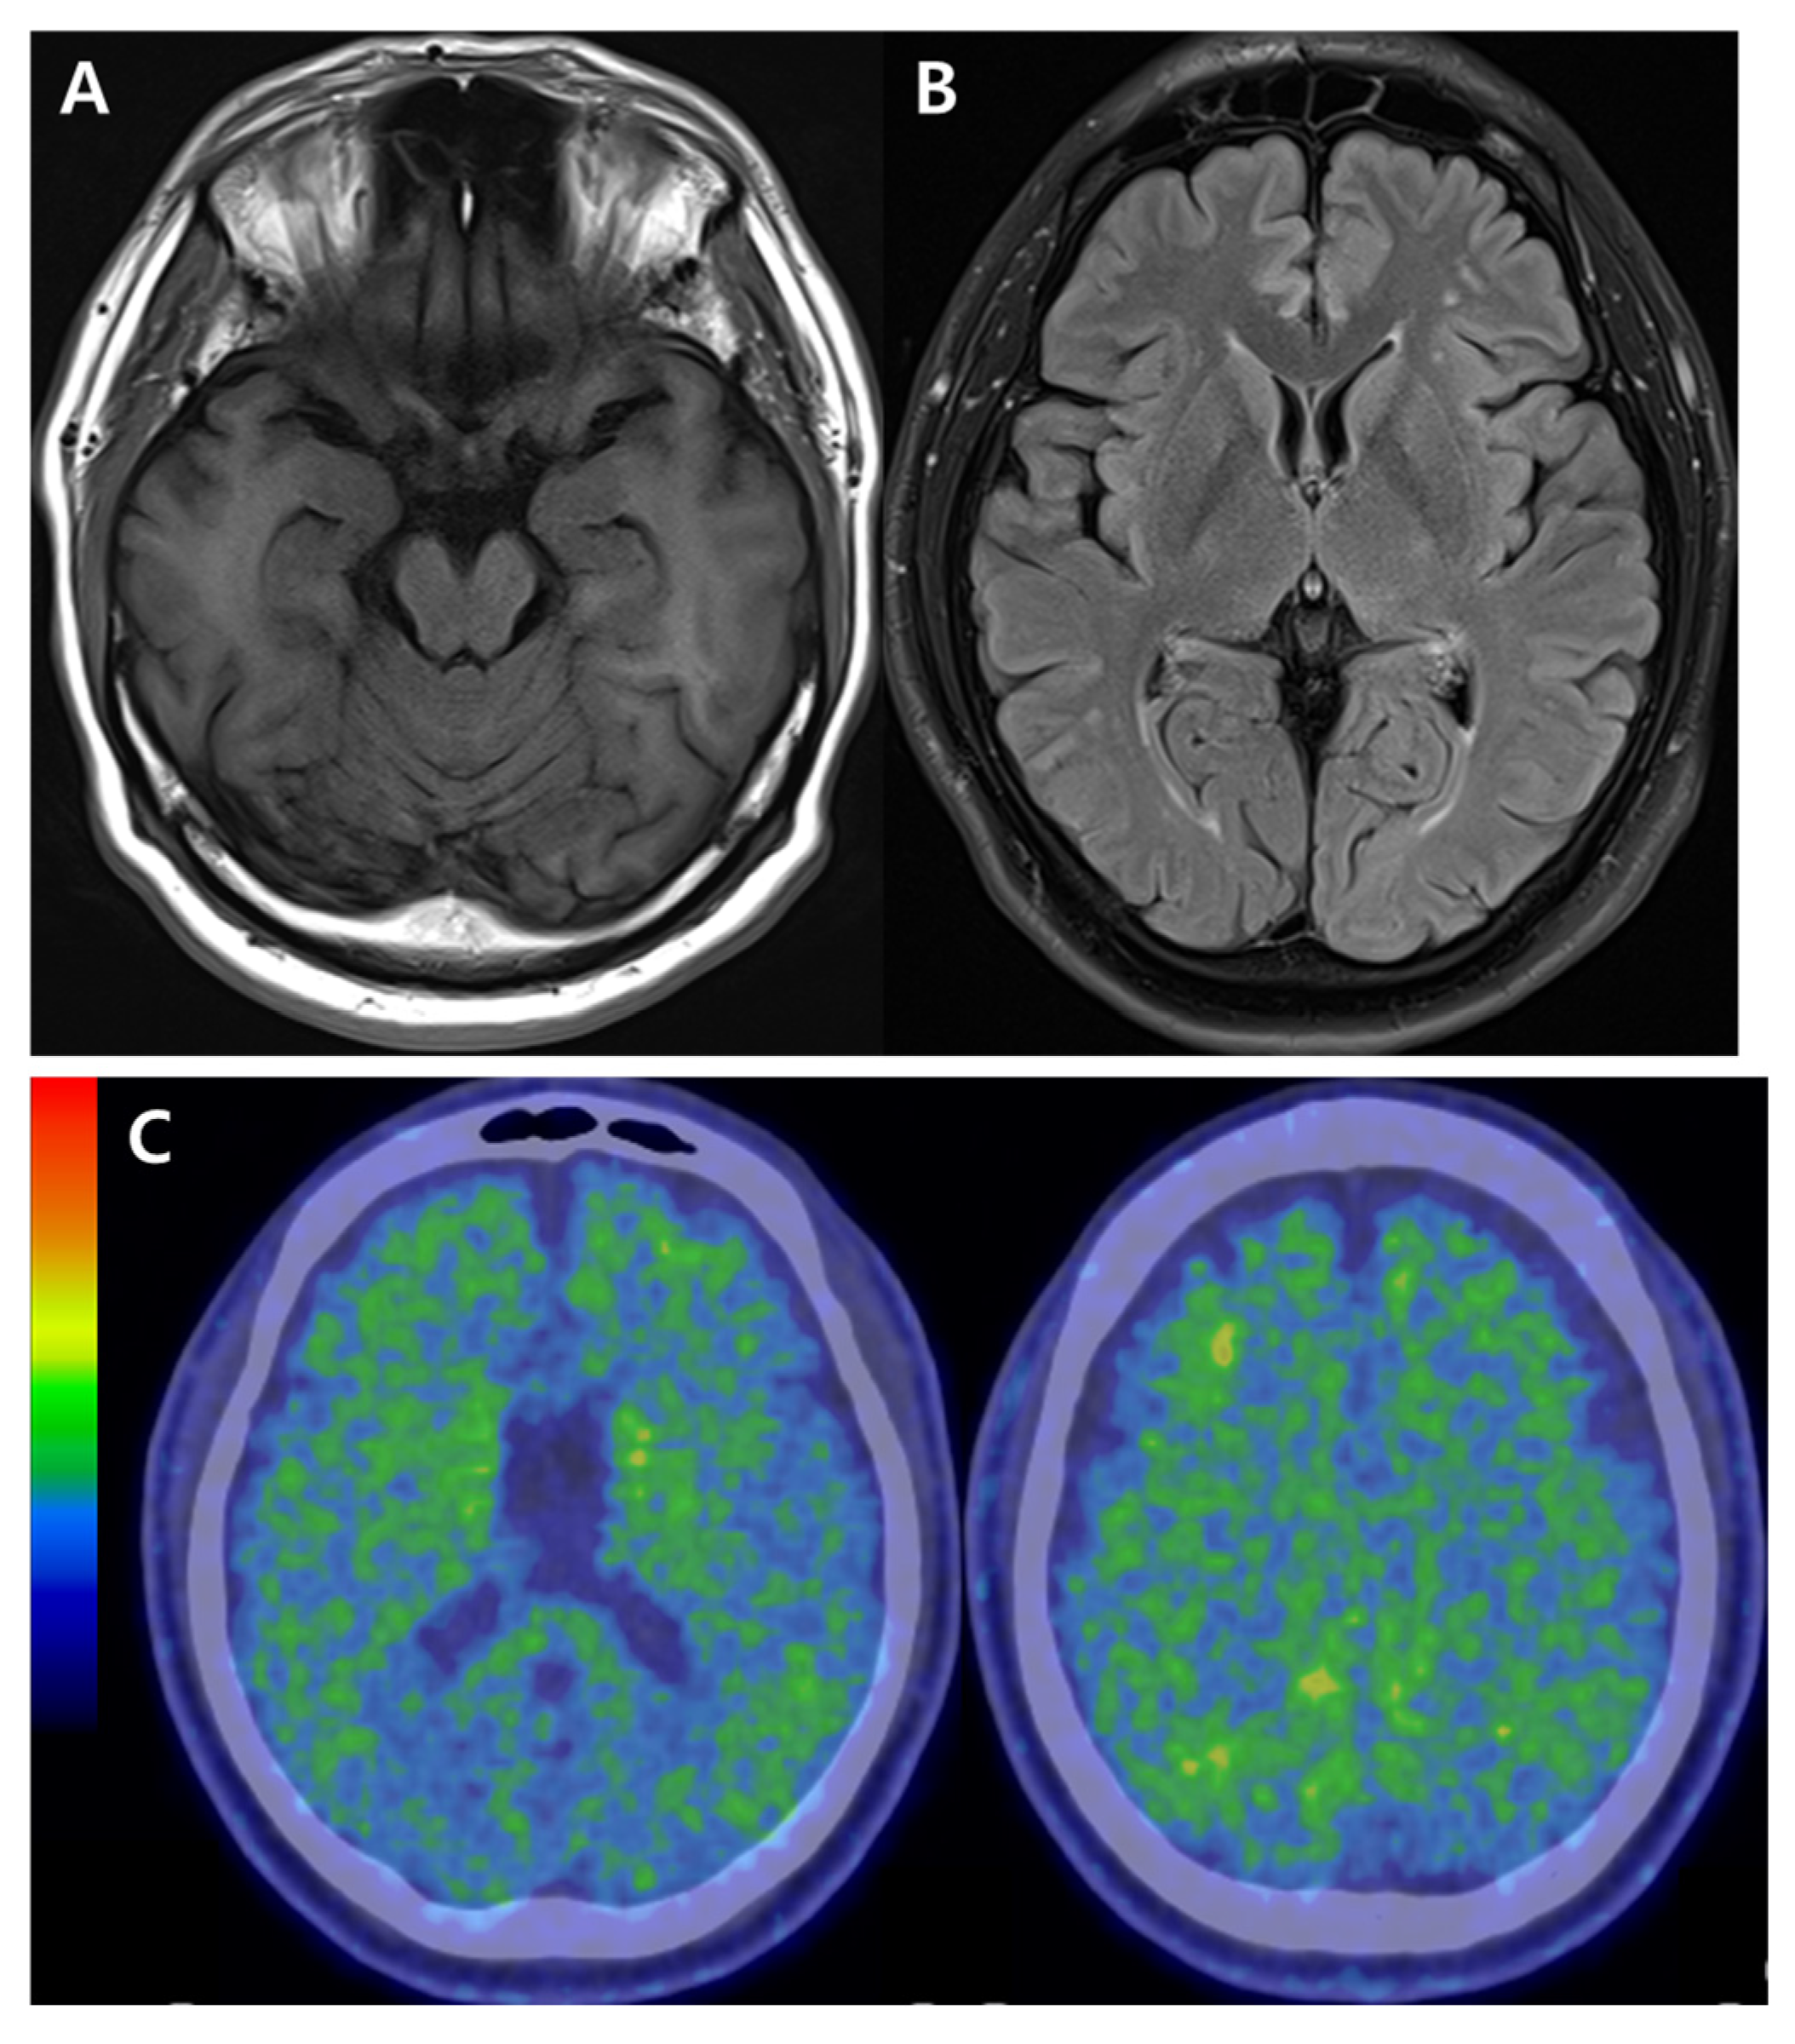

A previous neuropsychological assessment of the proband patient revealed deficits in attention, visuospatial function, short- and long-term memory, and executive functions. His clinical dementia rating (CDR) score was 0.5/3, with a sum of box (SOB) 2.5, and the mini mental status exam (MMSE) score was 27/30. The apolipoprotein E (APOE) genotype was E3/E3. The magnetic resonance image (MRI) indicated mild hippocampal atrophy and mild white matter hyperintensities (Figure 2A,B). There were no significant steno-occlusive lesions or aneurysms in the intracranial artery in magnetic resonance angiography (MRA). Amyloid positron emission tomography (amyloid-PET with 18F Florebetaben (FBB)-PET) showed amyloid positivity in several brain regions, including bilateral lateral temporal–frontal–parietal areas, posterior cingulate and precuneus (Figure 2C). During his initial visit to the hospital, the blood was drawn with heparin anti-coagulant and tested for amyloid ß (Aβ) oligomerization tendency with AlzOn (PeopleBio Inc., Sungnam, Republic of Korea) [8,9]. The AlzOn results were positive, with a value of 1.045 for the increased Aβ oligomerization tendency, confirming a high-risk profile. His treatment was started with Donepezil (10 mg/day). Two years later, the proband patient was retested with AlzOn, and the value was 1.009, indicating the continuous existence of Aβ progression and potential use of AlzOn in the clinical monitoring. A follow-up assessment two years later revealed a gradual progressive pattern of memory deficits, accompanied by an increase in depressive mood. His CDR, SOB, and MMSE scores were 1/3, 6, and 22/30, respectively, supporting gradual declines.

Figure 2. Neuroimaging data for the proband (III-1). (A). Magnetic resonance imaging (MRI) revealed mild hippocampal atrophy. (B). MRI showed a mild white matter change. (C). Amyloid-positron emission tomography (PET) indicated amyloid positivity in several brain regions (bilateral– lateral temporal, frontal, and parietal areas).